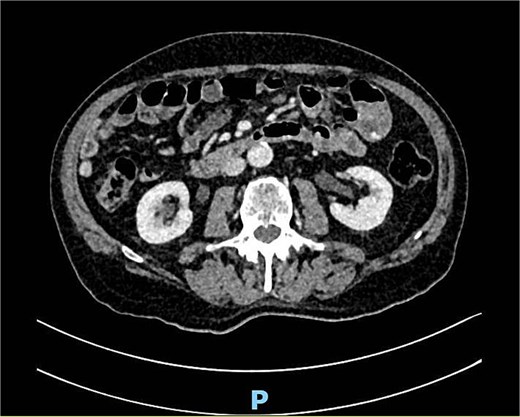

A new drop of the hemoglobin (6.3 g/dl) led to a CTA and transfusion of two more red blood cell concentrates. The CT scan showed a venous seepage in the small bowel, presumably the jejunum (Fig. 9). In a re-do gastroscopy we saw a JD (Fig. 10), but the origin of the bleeding could not be detected as only 20–30 cm jejunum could be reached. The following single-balloon enteroscopy until 2 m post the pylorus showed a pronounced jejunual diverticolisis with the largest diverticula located ⁓50 cm post the pylorus. In this region, there were also prominent blood vessels inside the diverticula detected, but without signs of an ongoing bleeding. Therefore no further intervention was done.